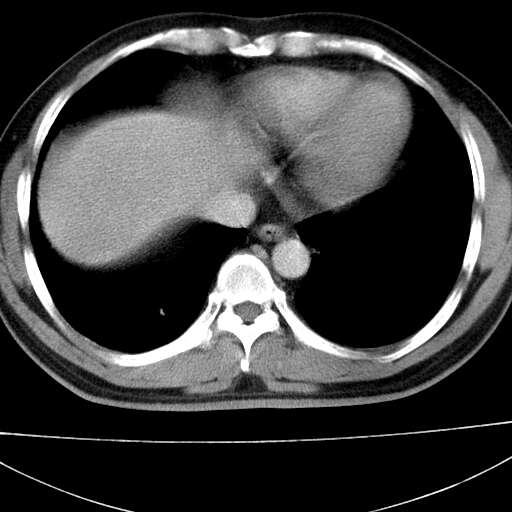

标题: CT21921:腹膜后腔肿物。患者男39Y。体检。增强扫描时间欠准

膈疝

左膈肌连续性中断,左侧膈疝可能性大.

考虑左肺下叶后基底段肺隔离症?胸膜间皮瘤?

左膈肌连续性中断,左侧膈疝可能性大

左下肺隔离症,可见从胸主动脉发出异常血管供应